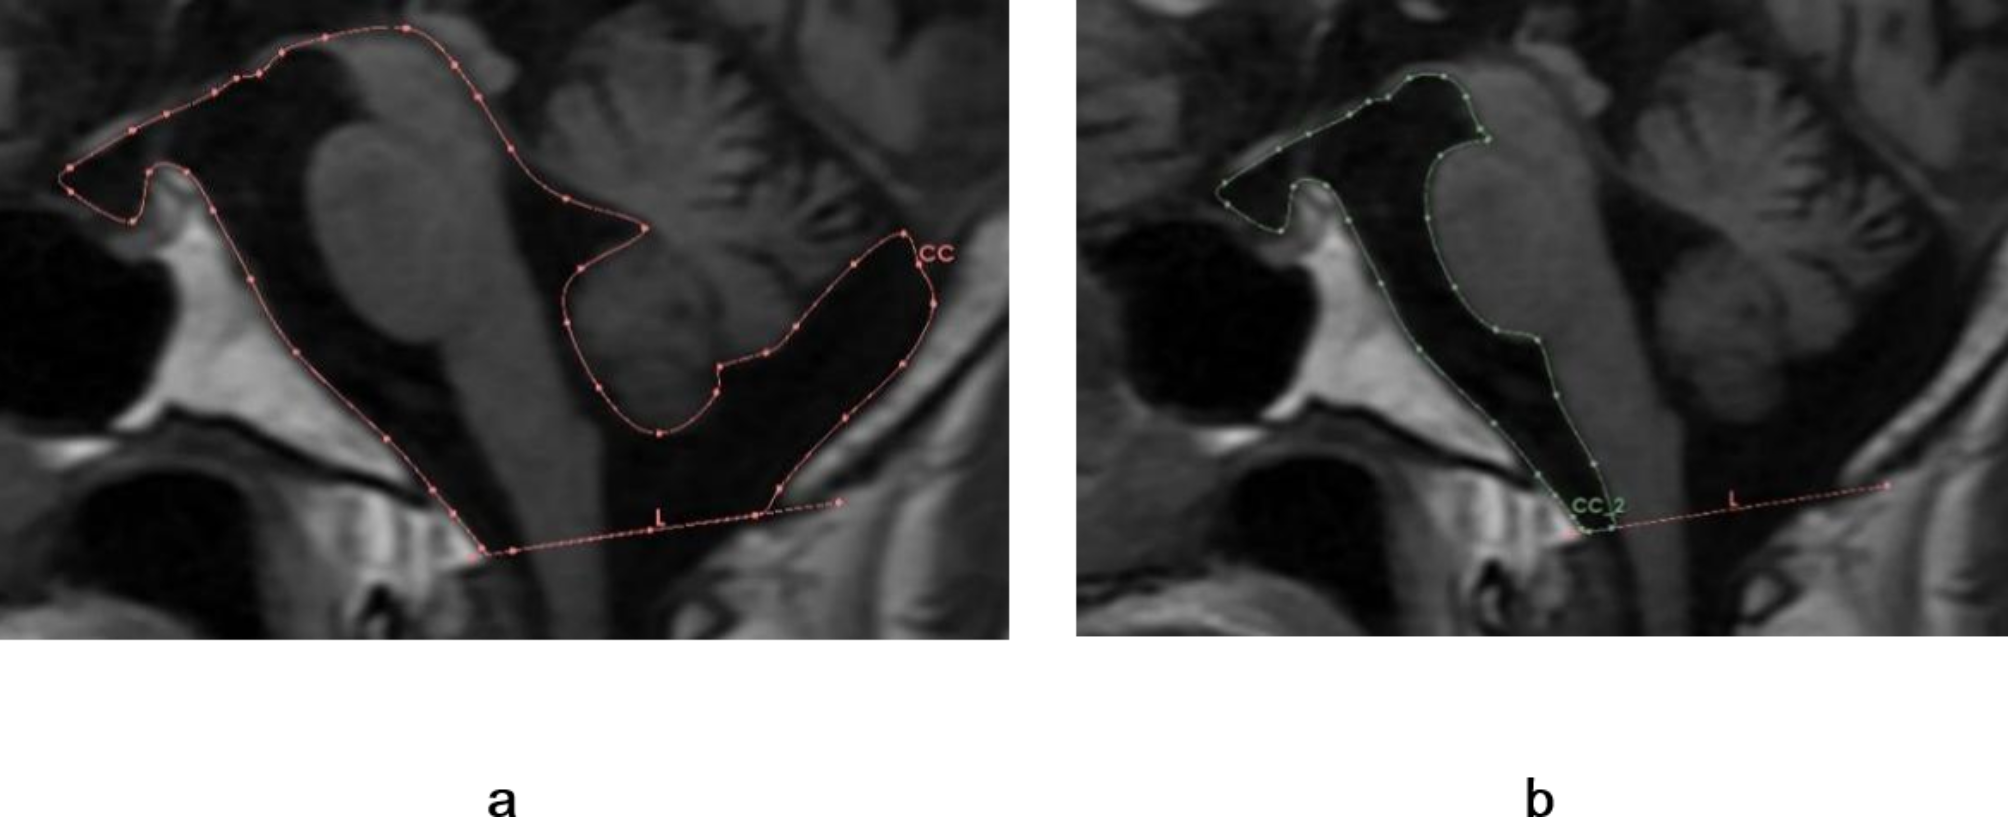

Fig. 4

Illustration of cisternal spaces surrounding the brainstem. (a) The total cisternal space is composed primarily of the interpeduncular, prepontine, medullary, and cerebellomedullary cisterns. The cerebral aqueduct and fourth ventricle are also shown. (b) Prepontine cistern in sagittal cross-section resembling a hammer.